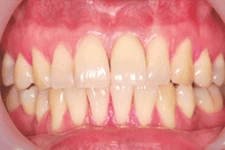

我們在植牙領域的突破,克服患者對手術的恐懼,也同時幫助患者告別了缺牙的痛苦,讓患者重新擁有一口完美的牙齒。

↑ 治療後:微創立即植牙恢復美麗外觀